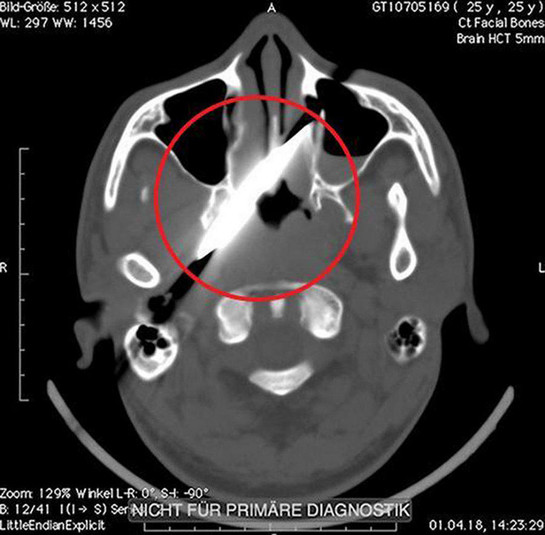

Рентген показал, что нож зашел на 10 см в голову, но не задел ни одной артерии

Удар ножом в глаз он получил во время пьяной драки в баре. После этого пострадавший как ни в чем не бывало отправился домой спать. На следующий день мужчине все же пришлось посетить медучреждение. Лезвия он не заметил, однако голова и глаз очень болели. Рентген показал, что нож зашел на 10 см в голову, но не задел ни одной артерии. Врачи даже решили перенести операцию на четыре дня, пока оформлялись необходимые документы.